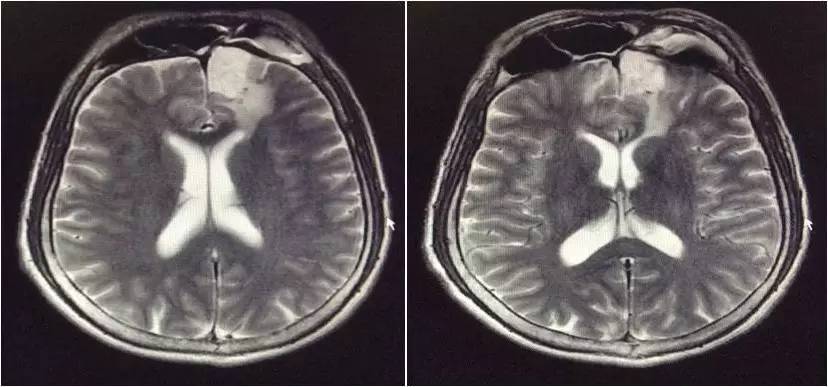

▼头颅MRI

2.脑脊液改变不除外结核感染,但头MRI改变非典型结核影像。左额叶病灶似以脑外为主,波及对侧及额窦,不排除慢性感染病灶急性破入蛛网膜下腔。左额叶病灶与脑脊液信号等信号,DWI也为低信号,说明非急性病变。

嗯,我们用的是国产的头孢曲松,没有进口的罗氏芬。DWI的高信号可以用血管炎解释吗?

血管炎都是多灶的,那个高信号太局限了,就是核心病灶周围的组织反应。不像血管炎。

真菌或结核可以引起脑底血管深穿支的炎症,有类似腔梗的影像改变。